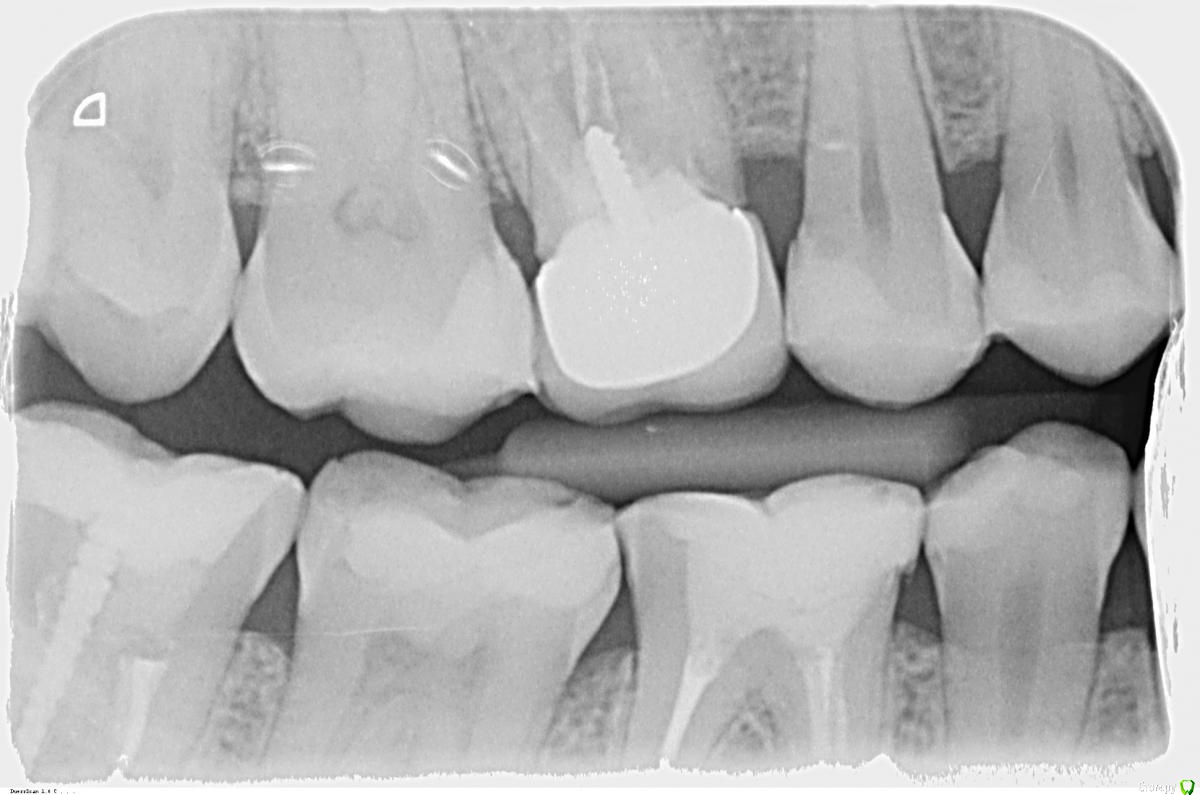

СветланаАндревна Опубликовано 26 октября, 2015 Поделиться Опубликовано 26 октября, 2015 (изменено) Здравствуйте! Сейчас нахожусь не в России, Великобритания.Кратко так. Речь о шестерке сверху справа. Где-то в 2000г депульпировали зуб, в 2005 поставили штифт и на нем слепили что-то похожее на зуб (по высоте был меньше, чем зубной ряд), в 2010 поставили коронку. Но как-то неудачно, в 2011 воспалилась десна, ее разрезали, почистили (налет?!), зашили, вроде более менее стоял. Последний год что-то не так с десной было, то ли чесалась, то ли что, какой-то дискомфорт, но толково врачу объяснить не смогла. Попросила на всякий случай рентген, посмотреть, не гниет ли под коронкой. Врач отказал, обосновав тем, что пока не снимем коронку не увидим что там. А десна немного воспалена, из-за того, что прилегающие 5 и 7 на контакте кариозные. Кариес пролечили, и я уехала в Британию. Через неделю десна воспалилась, и вылез гнойник. Пошли к местному стоматологу. Выписали антибиотик (амоксициллин?! вроде). Пропив, чуть полегчало, еще полоскала фурацилином. Приобрели ирригатор, с дуру еще им промывать стала. Опять вылезли гнойники. Сегодня наконец удалось опять к стоматологу попасть, говорит,раз антибиотик не помог, значит надо удалять. Попросила сделать рентген. Его и прилагаю. Плюс фото десны с гнойником Можно ли спасти зуб? Или все? Планирую ехать в Россию, попытаться спасти зуб, если это возможно. Сколько времени это может занять? пысы. Ситуация осложнена тем, что у меня ребенок маленький, придется оставить его папе на время поездки, а у него отпуск не резиновый. С собой брать не вариант, и дороже обойдется, и оставлять его в России некому пока я на прием к врачу ходить буду.. Изменено 26 октября, 2015 пользователем СветланаАндревна Ссылка на комментарий

krokomot Опубликовано 26 октября, 2015 Поделиться Опубликовано 26 октября, 2015 похоже на перфорацию корня, надо смотреть очно Ссылка на комментарий

DmitrySH Опубликовано 26 октября, 2015 Поделиться Опубликовано 26 октября, 2015 К эндодонтисту.Снять коронку, достать штифт, оценить состояние дна полости зуба, если все ок, то ревизия каналов. Дождаться закрытия "свища" и все в обратном порядке.А вот если выявятся проблемы с разрушением самого зуба ( что можно предположить по локализации очага воспаления) тогда уже по ситуации. 3 Ссылка на комментарий

x3m Опубликовано 7 ноября, 2015 Поделиться Опубликовано 7 ноября, 2015 ищите третьего стоматолога Полгода в каналах лечить нечего.Как Вам и отвечали, надо снять коронку, весь композит, извлечь штифт и оценить объем оставшихся тканей зуба, целостность дна (область зуба между каналами), отсутствие перфорации/трещины. Итого, вскрытие покажет:1. Зуб лечибелен (есть запас тканей, дно зуба целое, перфорации и трещины нет) - нашли все 4 канала, их перепломбировали, установили ВКВ и коронку. За недели 2 (+ / -) управитесь.2. Зуб нелечибелен (кариес глубоко под десной, трещина/перфорация, разрушено дно, невозможно перелечить каналы)- удалили и через 1-1,5 мес (если не сразу) установили имплантат. П.С. Что там чистить будут, кода "выдерут" - неважно, главное - чтоб чисто 3 Ссылка на комментарий